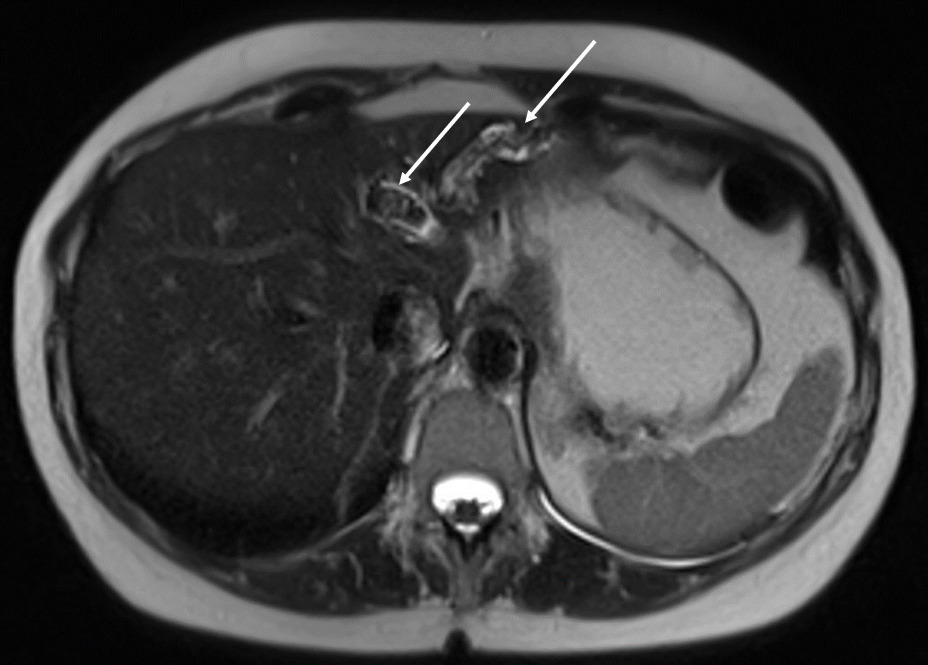

La cholangiographie par IRM est typiquement normale dans les formes habituelles, microlithiasiques, du syndrome LPAC. Elle n’est donc pas nécessaire au diagnostic dans la très grande majorité des situations. Elle doit être réalisée en cas de calculs intrahépatiques ou de dilatation des canaux biliaires en échographie afin d’évaluer le retentissement de ces calculs sur les voies biliaires et le parenchyme hépatique. Les calculs biliaires ne sont pas toujours visibles à l’imagerie par résonance magnétique (IRM), notamment quand leur taille est inférieure à 5 mm. Lorsqu’ils sont visibles, ils sont le plus souvent visualisés en hyposignal T1 et T2 sous forme de lacunes endobiliaires (fig. 2 A et 2B). Dans une série récente portant sur 125 patients suivis dans un centre expert et ayant tous eu une bili-IRM, 49 % présentaient des anomalies des canaux biliaires, parmi lesquelles 93 % de calculs intra­hépatiques et 38 % de dilatation des canaux biliaires.10 Ces anomalies morphologiques étaient plus fréquemment observées chez les porteurs d’un variant pathogène du gène ABCB4.